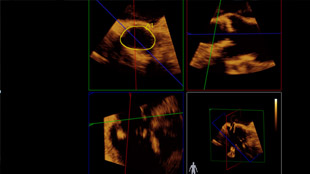

تساعدك القياسات الدقيقة للقوس الأورطي باستخدام البيانات ثلاثية الأبعاد في اختيار حجم الجهاز المناسب.